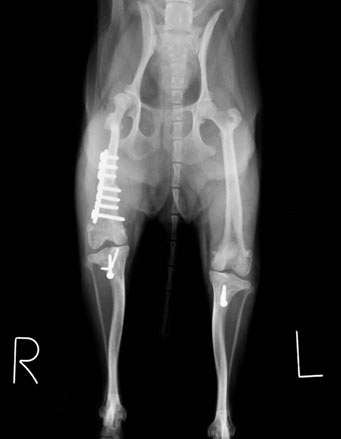

左右とも膝蓋骨の内方脱臼および大腿骨、脛骨の変形が認められます。 まだ子犬で、今のままではこの状態のままずっと歩けなくなることは間違いないと判断し、飼い主様とご相談し、両側膝蓋骨内方脱臼整復手術および、変形が強い右の大腿骨矯正骨きり手術を行いました。

大腿骨の骨きりおよびプレートにて矯正しました。滑車溝も形成を行いました。

最後に脛骨粗面の転植し、大腿骨-膝蓋骨-脛骨粗面のアライメントと整え手術終了としました。

手術後レントゲン:膝蓋骨は正常な位置に整復され、足もまっすぐになりました。 術後は1週間程で歩行できるようになり、2ヶ月ほどでほぼ正常なワンちゃんと変わらず元気に遊べるようになりました。膝蓋骨内方脱臼は先天的疾患で、このワンちゃんほど重度な症例は珍しいですが、比較的小型犬に多い後肢の疾患です。膝蓋骨がすでに脱臼しているが症状が無いわんちゃんも多く認められます。安易な経過観察は関節炎や前十字靭帯断裂症など様々な合併症の原因となるため、比較的早期の整復手術をおすすめします!